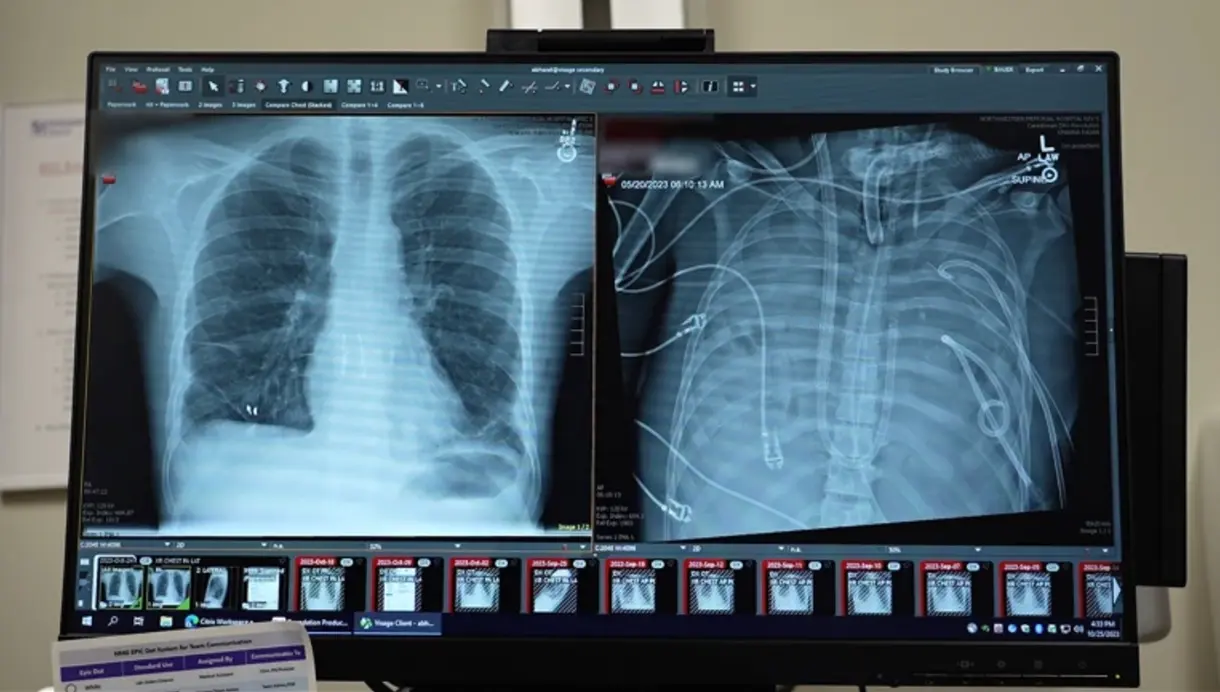

Rentgeno nuotraukose matyti 33 metų paciento naujieji plaučiai (kairėje) ir senieji plaučiai (dešinėje). Nuotr. „Northwestern Medicine“ / „Nature“.

33 metų vyras buvo hospitalizuotas itin sunkios būklės, nes jo plaučius sunaikino agresyvi infekcija, kilusi po gripo komplikacijų. Kadangi organai nebeatliko savo funkcijų, įprasta gyvybės palaikymo sistema buvo neefektyvi ir kiti gydymo metodai nebeveikė. Gydytojai turėjo ieškoti sprendimo, kaip pašalinti infekcijos šaltinį – plaučius, bet ir išsaugoti žmogaus gyvybę.